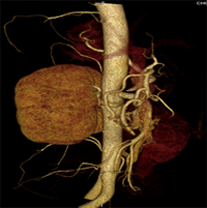

同一病人利用容積數(shù)據(jù)進行三維處理后,高品質(zhì)MPR和三維圖像上則清晰顯示了縱向排列的腹腔干與腸系膜上動脈相鄰近,血管發(fā)生變 異,近端血管閉塞,為臨床提供了精確的診斷信息。

從上面的例子可以看到,能否為臨床提供高品質(zhì)的三維影像成為了16層CT的核心價值,而東芝新一代的 全景三維16層CT擁有最為 先進的3項核心技術(shù),在16層核心價值上的表現(xiàn)自然值得期待。